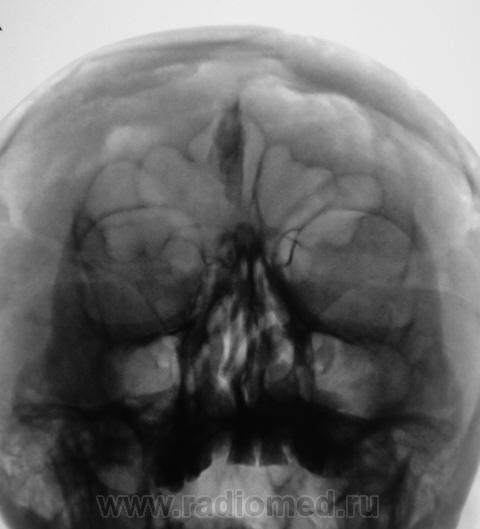

Обызвествление серповидного отростка.

А, меня, что-то смутила чешуя лобной кости...

Действительно, лобная кость какая-то "кучерявая", а в боковой проекции не доснимали?

Вены широковаты и боковые лакуны также выражены. Возможно на фоне остеопороза. Возраст, вероятно, немолодой.

Гиперпневматизация лобных пазух. Обызвествление серповидного отростка. Вероятно, повышение внутричерепного давления (сосудистый рисунок). Искривление носовой перегородки вправоsmiley. На нижнюю треть верхнечелюстных пазух "наслоились" пирамиды височных костей.